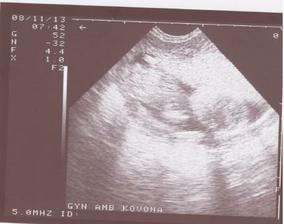

11.9.2008 - tak jsme viděli malou černou tečku a kvůli dovolené pana doktora za 14 dní jdeme o týden dřív tedy 18.9.2008 na kontrolu (první opravdovou těhotenskou 😀)